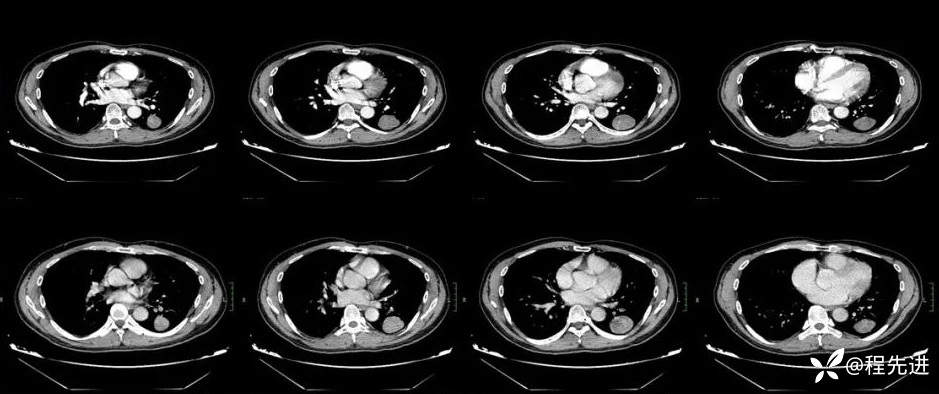

CT增强,上排动脉期,下排静脉期: